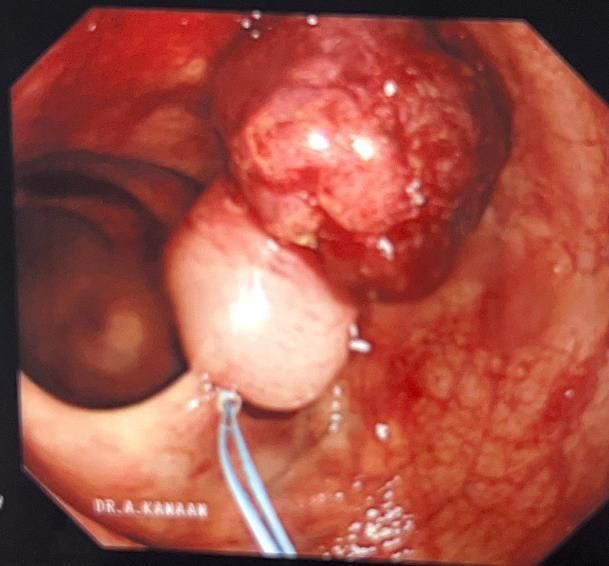

تمكن بفضل الله فريق من قسم الجهاز الهضمي والمناظير  في مستشفى الملك عبدالعزيز عضو تجمع مكة المكرمة  الصحي من إستئصال أورام حميدة من القولون لمريض يبلغ من العمر 47 عاماً .

أوضح استشاري ورئيس قسم الجهاز الهضمي والمناظير والكبد الدكتور عبدالرحمن كنعان الذي اجرى عملية المنظار " حضر المريض للعيادات الخارجية وهو يعاني من نقص حاد في الدم مع وجود دم مخفي في البراز وتم عمل الفحوصات اللازمة مما استدعى تنويم المريض لعمل منظار للجهاز الهضمي السفلي حيث تبين  وجود ورم يبلغ حجمه 4x3 سم والاخر 5x6 سم .

وبعد أخذ العينه اتضح بأن الأورام حميدة وقابلة للتحول تم إجراء عملية المنظار استغرقت 45 دقيقه من خلالها تم  استئصال الورم  بواسطة تقنية Endo loop  دون الحاجة للتدخل الجراحي.

حيث تكللت العملية  بالنجاح وتماثل المريض للشفاء وغادر المستشفى وهو بصحة جيدة دون أي مضاعفات ولله الحمد.